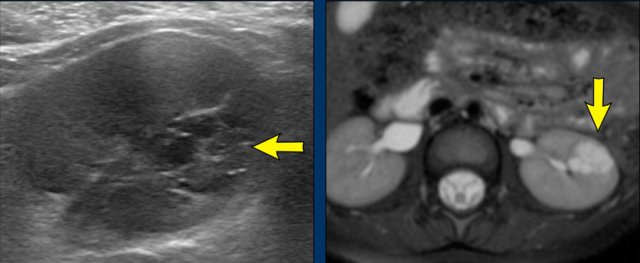

Claw sign Claw sign

Claw sign

This sign in renal tumors is useful in determining that the tumor arises from the kidney rather than is located adjacent to the kidney and distorts the outline.

The claw sign refers to the sharp angles on either side of the mass, which the surrounding normal parenchyma forms when the mass has arisen from the kidney.

Images

Left sided Wilms' tumor in a one-year-old girl.

The remnant of the kidney is draped over the tumor, the “claw sign”.